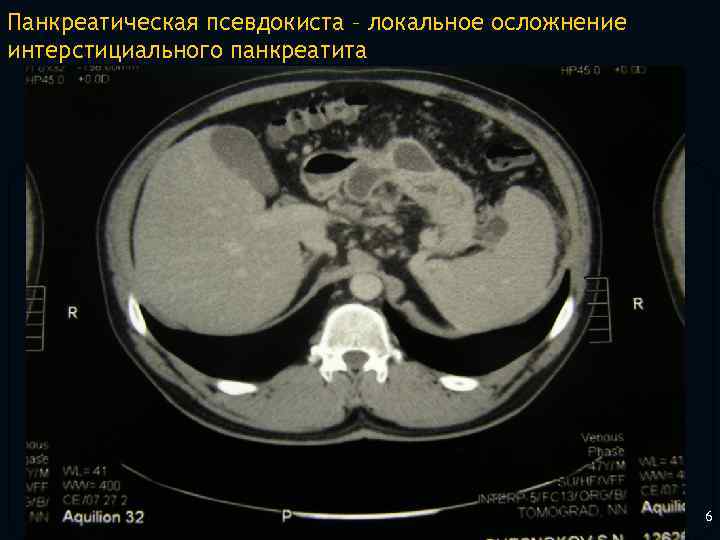

Панкреатическая псевдокиста – локальное осложнение интерстициального панкреатита 5

Панкреатическая псевдокиста – локальное осложнение интерстициального панкреатита 6